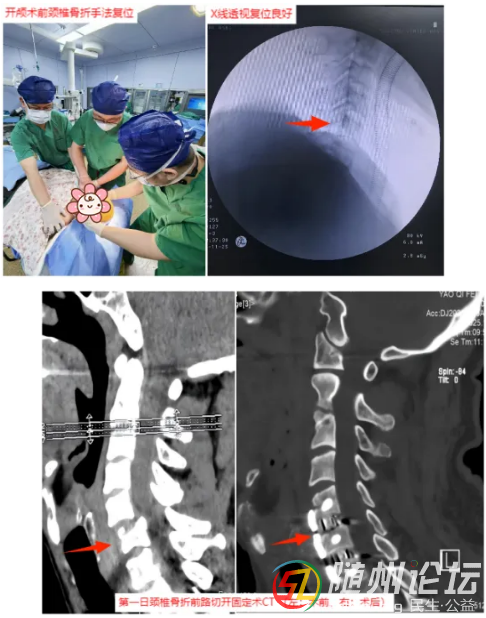

隨即,搶救團(tuán)隊(duì)爭(zhēng)分奪秒。脊柱外科團(tuán)隊(duì)首先對(duì)頸椎進(jìn)行手法復(fù)位,為后續(xù)手術(shù)創(chuàng)造條件;隨后,神經(jīng)外科團(tuán)隊(duì)立即進(jìn)行開顱手術(shù),精準(zhǔn)清除腦內(nèi)血腫,妥善處理出血點(diǎn),并將碎裂的顱骨修復(fù)還原;鑒于頸椎骨折仍需穩(wěn)固內(nèi)固定以最大限度保護(hù)脊髓功能,緊接著,脊柱外科團(tuán)隊(duì)再次手術(shù),對(duì)頸椎進(jìn)行內(nèi)固定,穩(wěn)定骨折部位,解除對(duì)脊髓的壓迫。整個(gè)救治過(guò)程環(huán)環(huán)相扣,緊張有序。